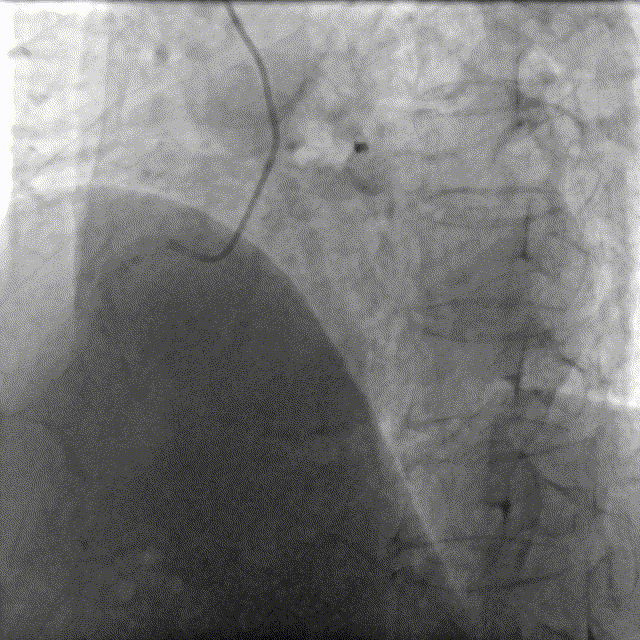

于前降支中段近段口串联2.5mm×18mm、3.0mm×18mm DES。

前降支开口精确定位植入3.5mm×18mm DES。

2.5mm-3.5mm后扩球囊后扩张。

最终结果满意,复查IVUS支架膨胀、贴壁良好!